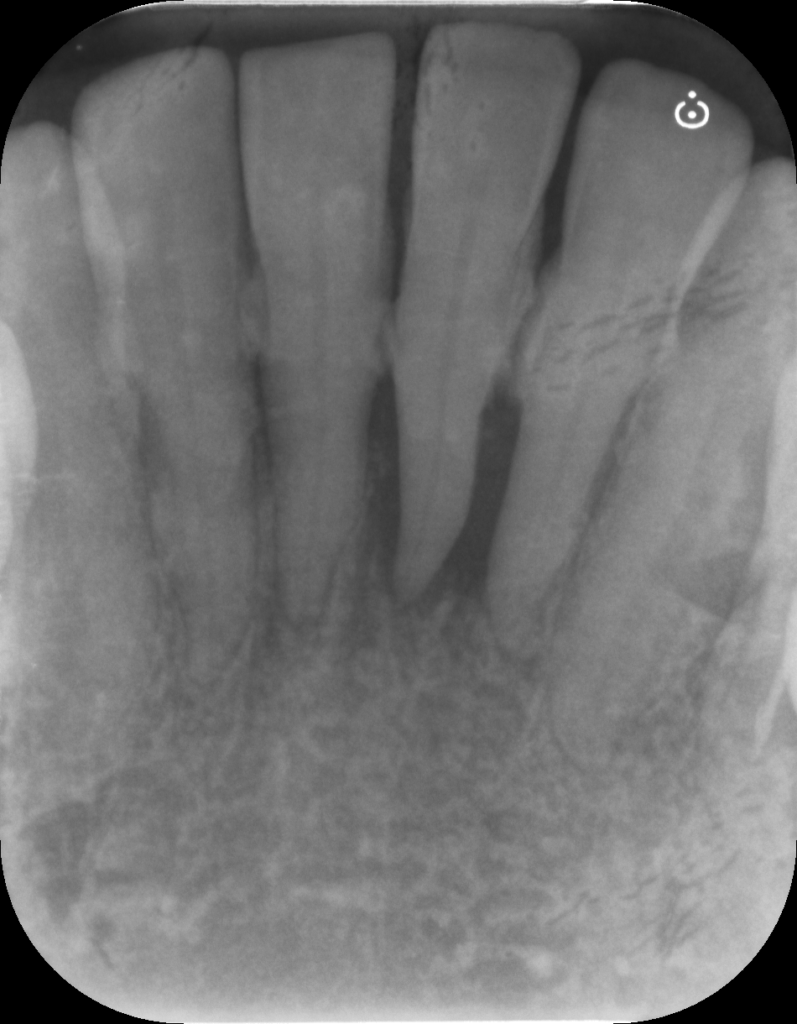

↑治療前後で骨の状態が改善しています。現在は隣の歯と固定して経過を見ています。

↑レントゲンで骨吸収を認めます。歯肉を切開すると実際に骨がありません。

複数の部位で歯周外科治療をおこないましたが、まだタイミングを探っている場所もあります。SRPの反応を見ながら、介入のタイミングを見ています。